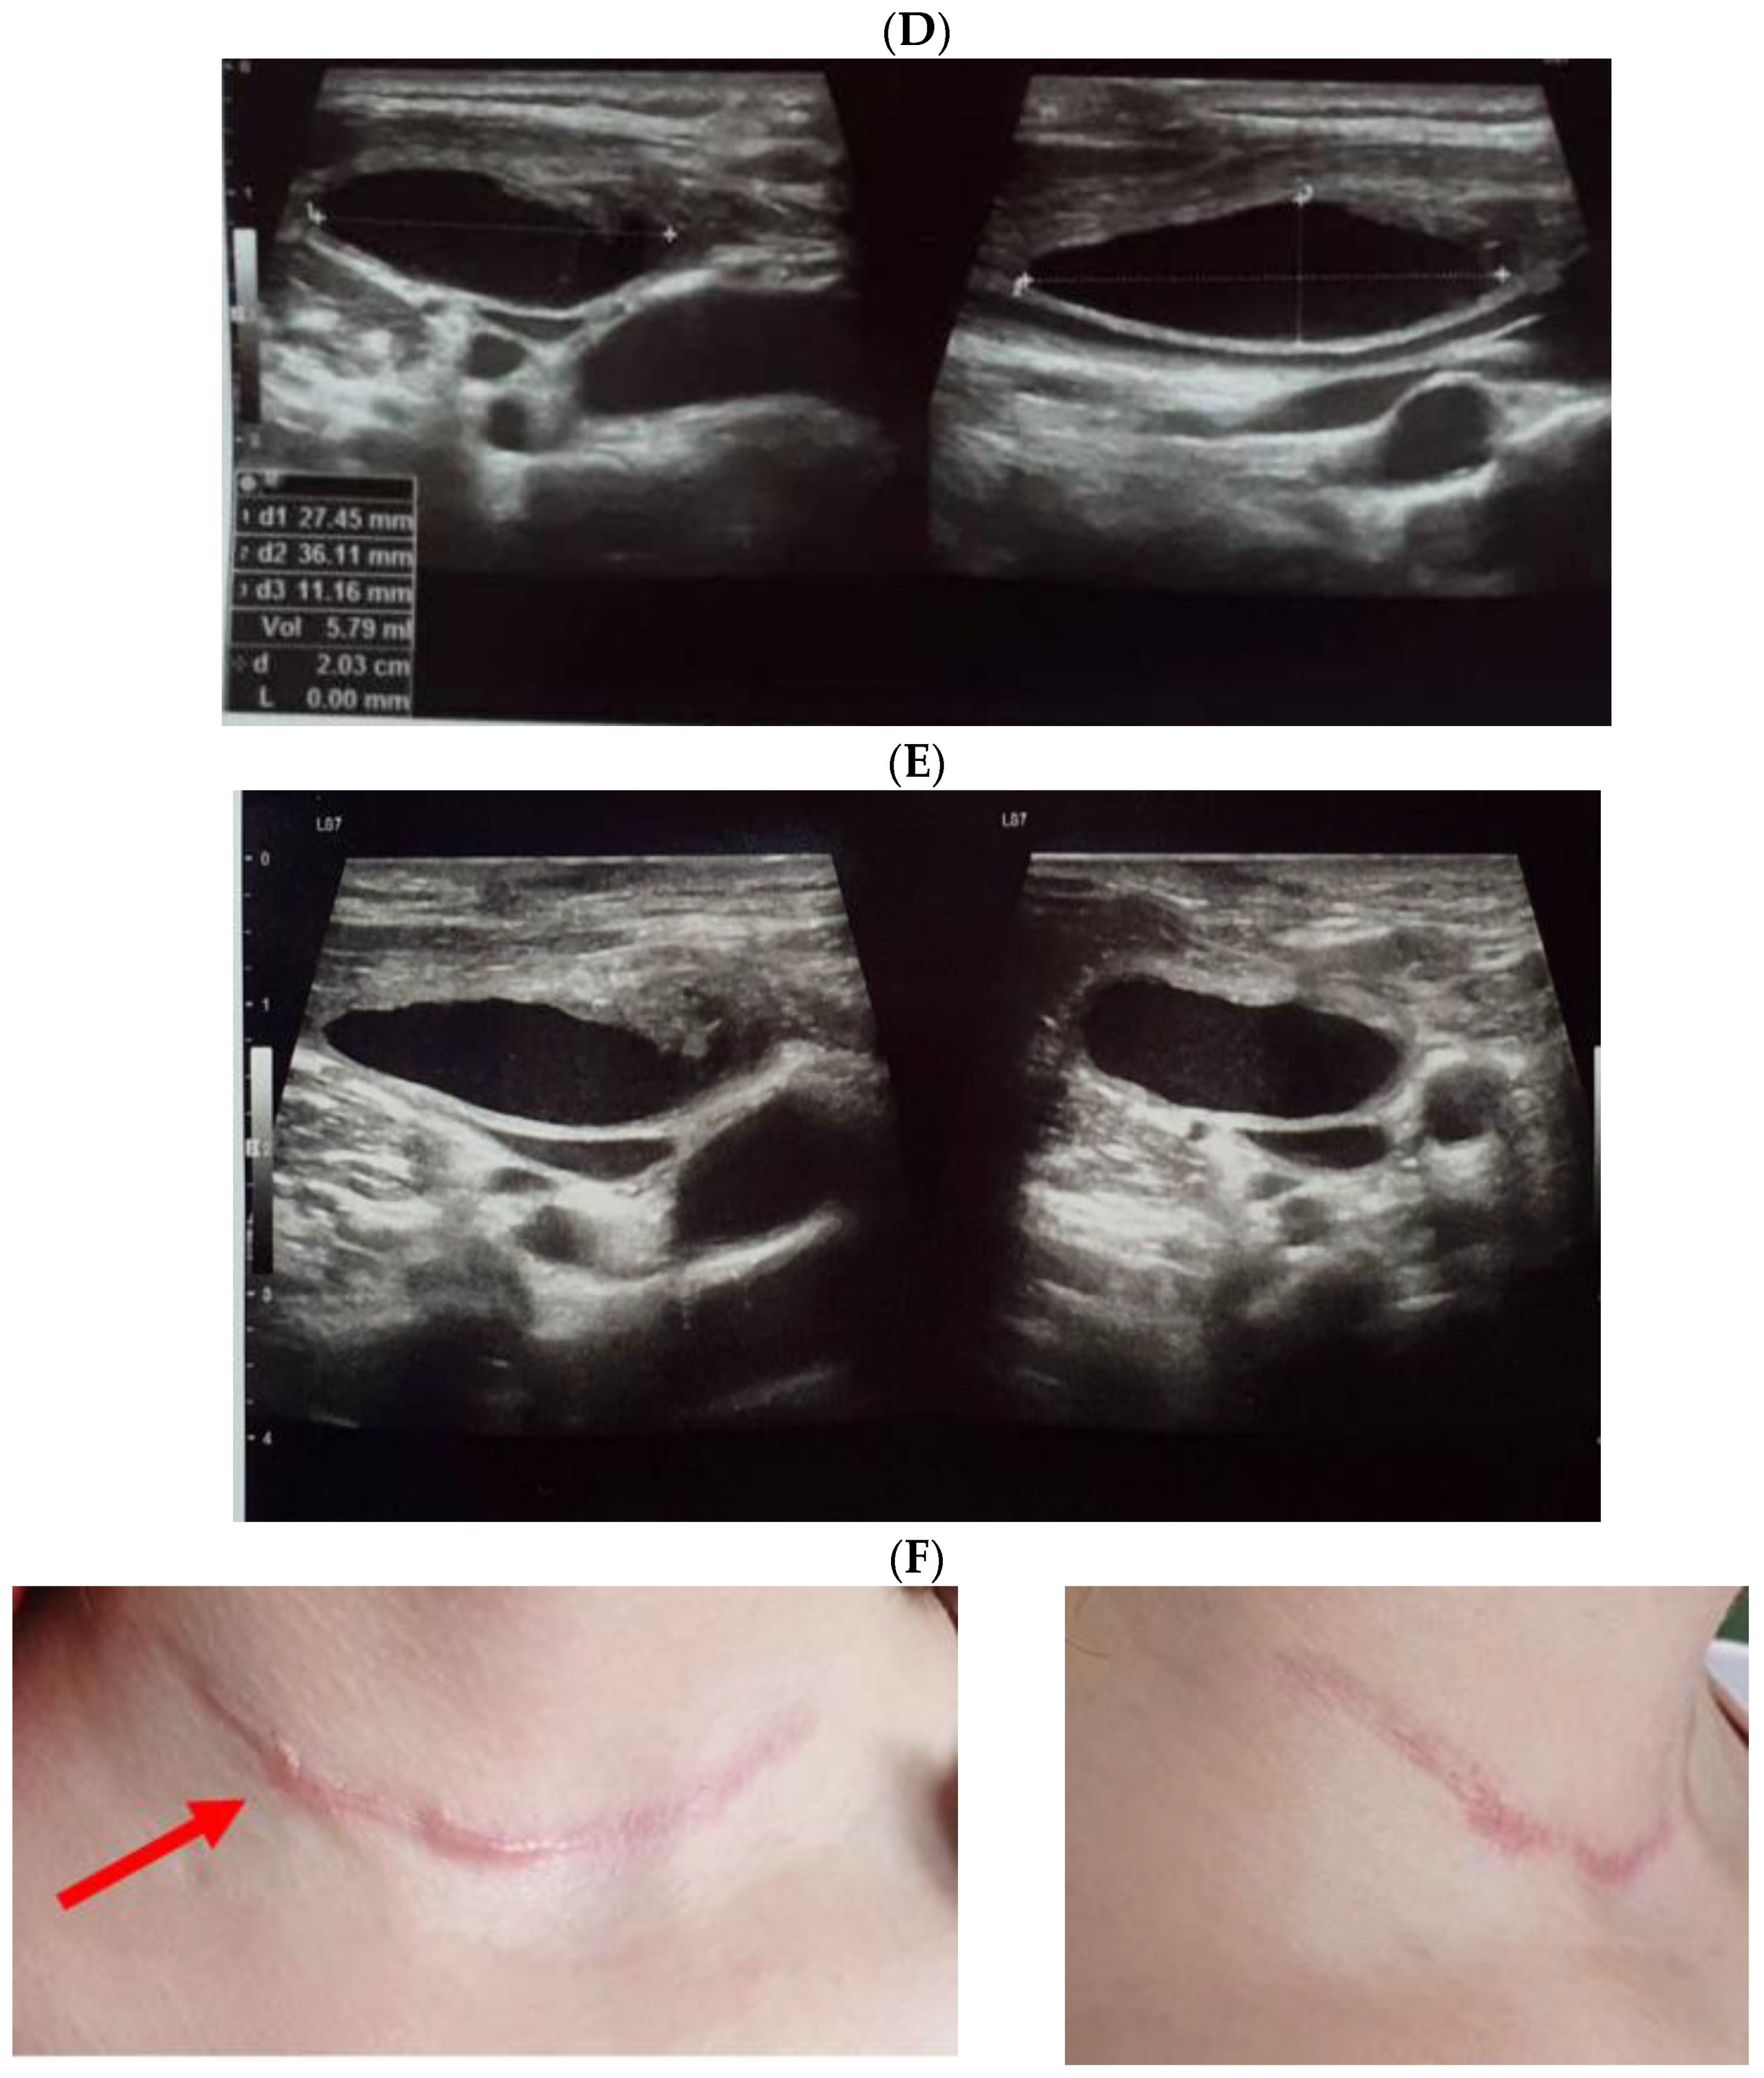

3.2. Thyroidectomy/Lymph Nodes Dissection and Lymphocele/Chylous Leakage

3.3. Post-Thyroidectomy HS and Lymphocele